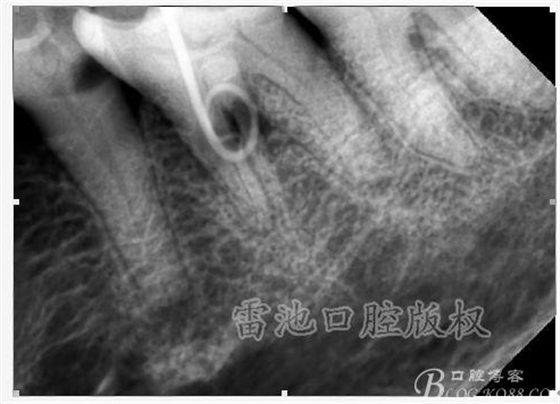

C、牙根的折裂與隱裂 包括橫折,縱折,或者斜折,外傷類的不用討論,主要是某些特殊原因比如牙齒本身結(jié)構(gòu)先天性缺陷再配合后天因素如牙合創(chuàng)傷、咬合平衡發(fā)生改變導致應力集中,或者某次瞬間的咬合暴力等一種或者多種因素作用的結(jié)果,具體什么原因這個要從多方面因素權(quán)衡來判斷,比如牙齒的松動度,詢問病史,找不出其它原因時的重點懷疑,牙齒本事是否處于合應力集中的區(qū)域,是否有不良修復設計等等,具體可以通過臨床“理化檢查(冷熱,叩診等)”再結(jié)合數(shù)值化小牙片,牙髓活力測定,以及CBCT等來綜合判斷,重點懷疑牙為上頜的4/5的頰或者腭根,尤其是4或者5的遠中已是游離缺失或者單端橋等,6的腭根以及下頜的4/5/6都是重點懷疑對象,而最難診斷的是牙根的隱裂,即使使用CBCT有時候也沒辦法確診;